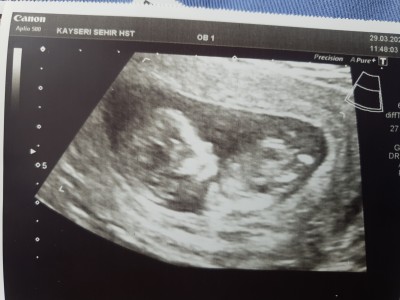

Merhaba teyzelerimiz biz büyüyoruz  12+5 olduk  henuz cinsiyetimiz belli degil doktor teyzemiz erkege benziyor  dedi ama ben meraktan çatlıyorum   sizce nedir  tehminleri alalim

Gebelik haftası 12+5